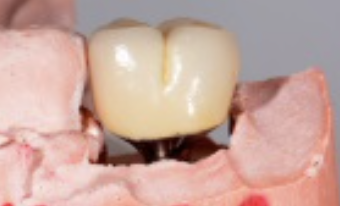

Following the recommendations of Yi, the transmucosal portion of the prosthetic connections should be flat or concave in profile diverging no more that 30 degrees from the long axis of the implants.19 Standard abutment profiles which are flat or convex in profiles are good examples to follow (Figure 19). Following Yi's recommendations individual posterior custom abutments with narrow implants should have flat or concave transmucosal profiles like a standard implant abutment with convex intaglio shapes like pontics that are cleanable with dental floss19 (Figure 20 through Figure 28).

(2828.) Premolar custom abutment.

Figure 28

(26.) Premolar custom abutment.

Figure 26

(27.) Premolar custom abutment.

Figure 27